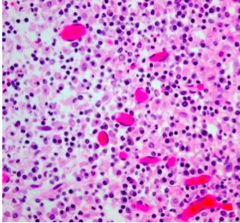

Presence of lymphoid tissue

lymphocytes have very little cytoplasm on H and E so they always look blue

malignant cells showing pleiomorphic, anisocytosic, and discohesive feature

Back